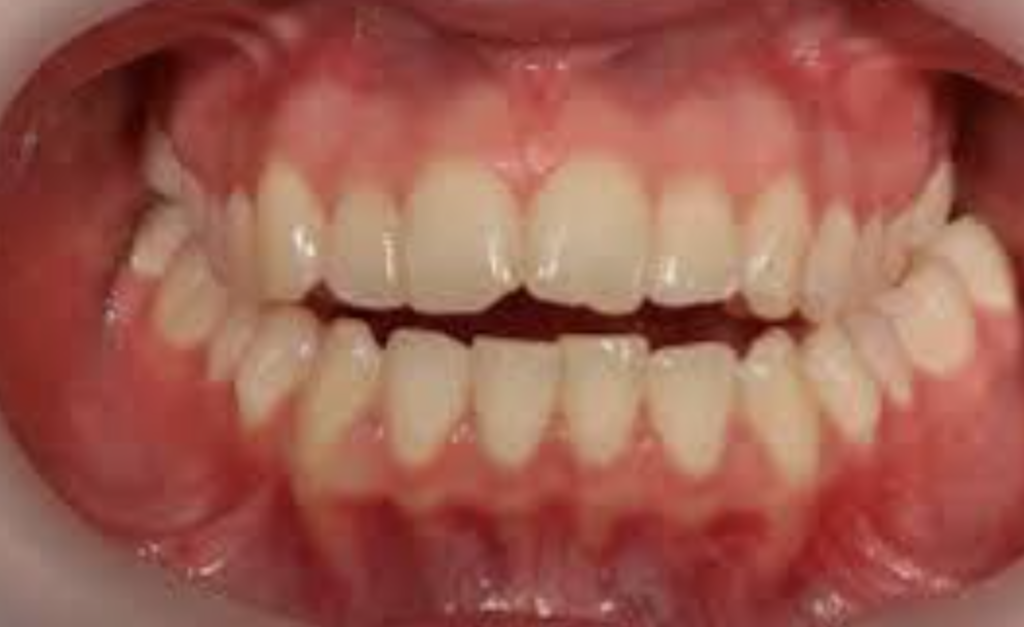

Cas Clinique 2 : Béance Antérieure d’Origine Fonctionnelle — Prise en Charge Étiologique

Patient : Karim, 10 ans. Adressé par son médecin traitant pour “dents qui ne se touchent pas devant”.

Présentation : Béance antérieure de 5 mm, overbite négatif. Classe I squelettique, face normodivergente. Déglutition atypique avec interposition linguale antérieure systématique. Respiration mixte oro-nasale. Pas de macroglossie cliniquement évidente.

Problématique : Béance fonctionnelle pure, non squelettique. L’anomalie est entretenue par une dysfonction linguale persistante. Traiter mécaniquement sans rééduquer la langue ne servirait à rien.

Prise en charge :

- Bilan ORL → amygdales légèrement hypertrophiques, végétations adénoïdes → adénoïdectomie + rééducation orthophonique de la ventilation nasale.

- Rééducation de la déglutition (myothérapie linguale, 6 mois).

- Pose d’une plaque palatine avec perle de Tucat pour modifier la posture linguale de repos.

- Après normalisation fonctionnelle : ELN nocturne pour consolider les acquis.

Résultat attendu : Fermeture spontanée de la béance antérieure dans les 6-12 mois suivant la normalisation fonctionnelle. Stabilité conditionnée au maintien des nouvelles habitudes linguale et ventilatoire.

Point pédagogique : Une béance d’origine fonctionnelle se ferme d’elle-même dès que la cause est supprimée. Le rôle du praticien est ici principalement étiologique, non mécanique.